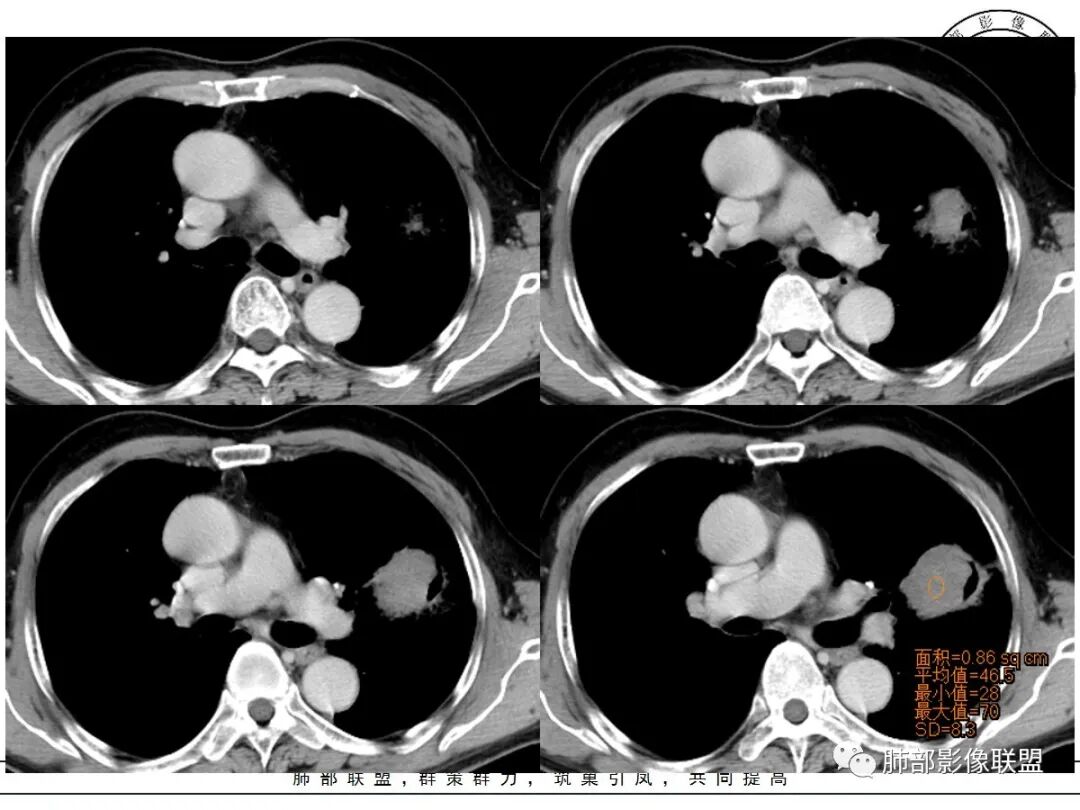

强化如何?

生来征服~浪子:

强化有疑问,前面感觉有低密度的,有些图好像又均匀

小锁:

不均匀中度强化

尘缘:

不均匀轻中度渐进强化。

这个空洞的性质很重要,对最后诊断结果影响大,如果中间没有曲菌球,那就是偏心空洞,指向恶性,如果是曲菌球引起的新月形改变,那就不一定。至于到底是曲菌球还是偏心空洞,需要仔细看看强化情况。

不均匀性强化,远端坏死比较明显

如果强化明确,那就可以排除曲菌球。

2、偏心空腔病灶,气腔略呈新月形,壁不规则,腔内结节相对密实,明显强化且不均,支持新生物而非曲菌球等。炎性空洞多有强化环。

3、病变强化较明显,其内隐约显示多发小斑片状无强化灶,可疑边界不清小灶坏死区。病灶内血管影浅淡、模糊不规则。